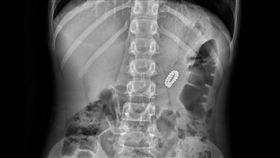

玩具不見了 4歲兒吞下27顆磁力球

小孩自己玩玩具時家長真的非常注意,尤其小朋友總有一段...

男童誤吞61顆磁球 腸道中串成項鍊

大陸黑龍江哈爾濱日前發生兒童誤食事件!一名6歲男童誤...

2歲童誤吞磁力球 腸道穿孔險喪命

大陸江西一名2歲男童近日常常無緣無故哭鬧,看完醫生仍...